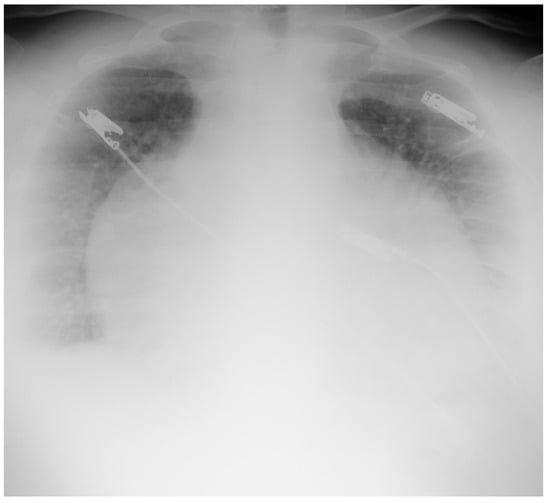

4.1.2. Chest X-ray